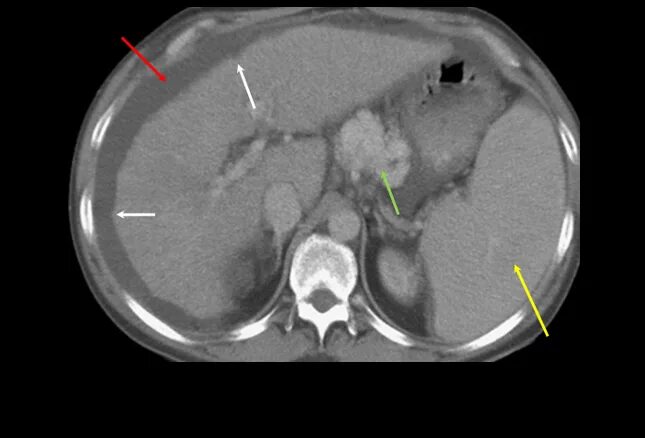

Асцит в малом тазу